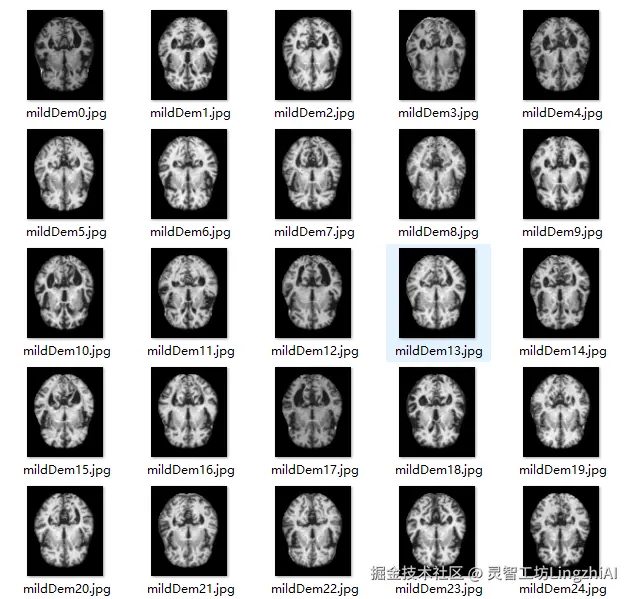

我们的数据集包含四个分类类别:

• NonDemented (正常): 无痴呆症状的健康个体

• VeryMildDemented (极轻度痴呆): 认知功能轻微下降

• MildDemented (轻度痴呆): 明显的认知功能障碍

• ModerateDemented (中度痴呆): 严重的认知功能损害

在这里插入图片描述

数据集采用标准的训练/测试分割,确保模型的泛化能力。